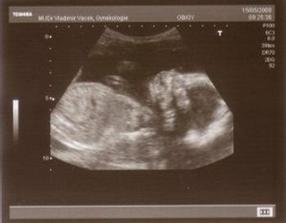

15.5.Podrobný UTZ máme za sebou a vše máme na správném místě,měříme 20-22cm a máme 475gr tak že už sme pořádný chlapisko🙂